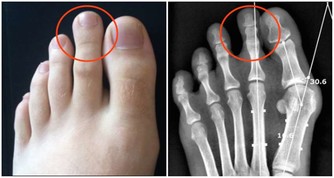

1、易得齲齒

由於兒童睡眠時間長,睡眠時口腔處於靜止狀態,唾液分泌減少,對牙齒的清潔作用減弱,有利於細菌繁殖。

口腔中殘留的糖容易被細菌分解發酵,產生酸性物質,侵蝕牙齒。